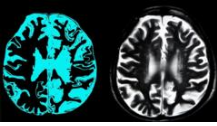

First drug that can slow Alzheimer’s dementia

A US drug company says it has created the first therapy that could slow Alzheimer’s disease, and it is now ready to bring it to market. Currently, there are no drugs that can do this – existing ones only help with symptoms.